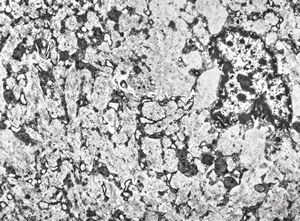

M, 1y. | glycogenosis type I. - liver